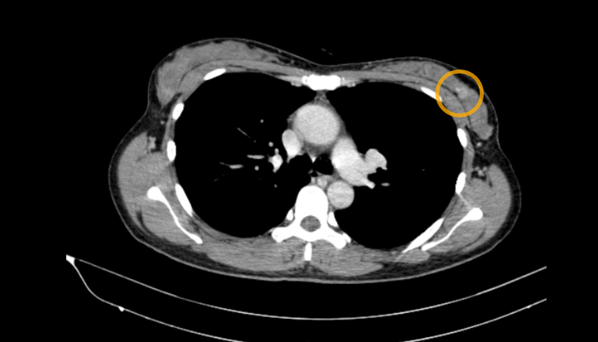

- Chụp cắt lớp vi tính ngực: Nốt bán đặc thùy dưới phổi phải ~6mm, các ổ ngấm thuốc kém hai vú, kích thước ~14x11mm

Hình 3. Hình ảnh CT lồng ngực: Ổ ngấm thuốc kém vú trái (vòng tròn vàng)